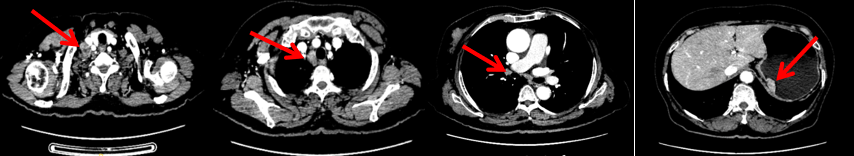

颈胸腹盆腔CT

右乳外上象限占位,考虑乳腺癌;右侧锁骨上、上纵隔及右肺门多发淋巴结转移(较大者24*15mm)。胃贲门处小弯侧胃壁明显增厚(26*12mm),考虑胃癌可能,周围脂肪间隙清;颈部未见明确异常。头颅MR未见脑转移。

2024-11-5复查CT:右乳外上象限占位(11mm×9mm),较前明显缩小;上纵隔及右肺门多发淋巴结转移缩小;右锁骨上区淋巴结较前增大。余部位未见肿瘤转移及复发征象。

头颅+鼻咽部+颈部MR:右侧锁骨上区、所见上纵隔多发肿大淋巴结,考虑转移瘤。脑、鼻咽部未见明显异常。